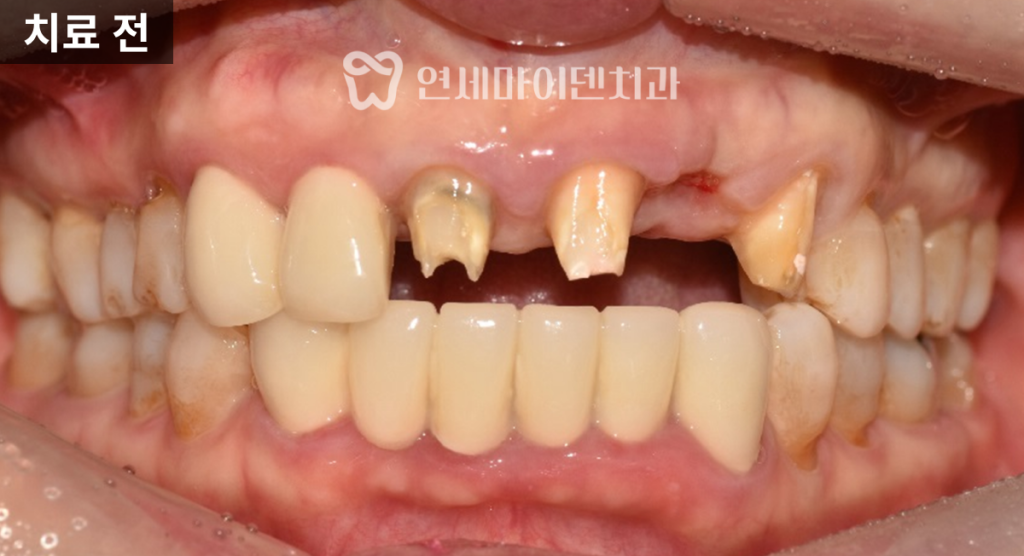

이번 케이스는

앞니가 반복적으로 붓고

고름이 생기며

발치 가능성까지 거론되던 상황이었습니다.전치부 앞니 네 개가

스플린트 크라운, 즉 여러 치아가

하나로 묶인 보철 형태로 제작되어 있었고,

이로 인해 염증 부위를

명확히 구분하기 어려운 상태였습니다.

스플린트 크라운은

단기적으로 흔들림을 줄이는 장점은 있지만,

치실 사용이 어렵고

각 치아를 개별적으로 평가하기 힘들어

염증을 늦게 발견하는 단점이 있습니다.이런 경우 문제가 상당히 진행된 뒤에야

증상이 겉으로 드러나는 경우가 많습니다.염증 앞니 치료 계획